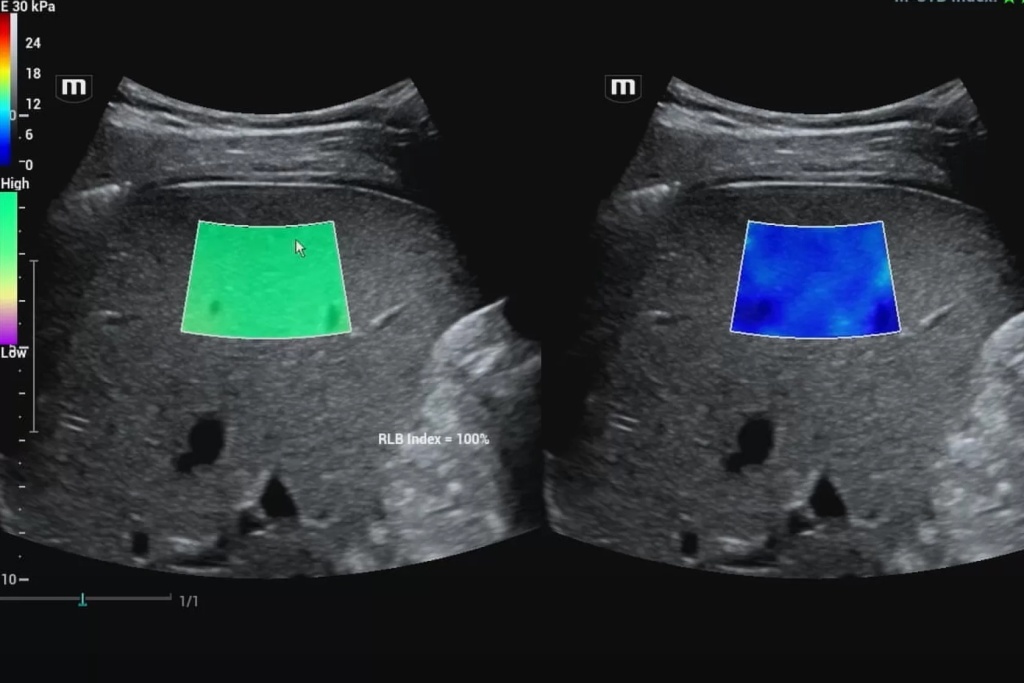

С применением методик эластографии жесткость интересующей нас зоны поверхностно-расположенных и внутренних органов может быть оценена и представлена в виде цветовой эластограммы, наложенной на изображение в В-режиме, и количественно. Это лежит в основе дифференциальной диагностики различных патологических изменений в структуре органа.

В данном случае получение абсолютных значений модуля Юнга (характеризующего жесткость тканей) невозможно, так как его значения зависят от приложенной силы, величина которой не стандартизирована и неизвестна. Поэтому проводится сравнение величины деформации, или стрейна. При воздействии одинаковой силы менее деформируемые ткани являются более жесткими, а более деформируемые – менее жесткими. Ультразвуковой сканер, работающий в специальном режиме, позволяет оценить и сравнить величину деформации тканей в окне опроса и картировать их соответствующим цветом, а также провести полуколичественную оценку – определить отношение деформации в зоне интереса и референсной (условно здоровой) ткани – StrainRatio.

Эластография сдвиговой волной позволяет получить абсолютные значения жесткости исследуемой ткани. В основе данного метода лежит оценка скорости распространения поперечной (боковой) волны, которая может вызываться кратковременным механическим воздействием определенной силы и продолжительности на поверхность тела пациента (это так называемая транзиентная эластография) или сфокусированным усиленным акустическим импульсов в толще исследуемой ткани (именно данные методики в литературе обозначаются как эластография сдвиговой волной). Они в свою очередь подразделяются на методики точечной и двумерной эластографии.

Также стоит сразу коснуться терминологии. Все методики можно обозначать как «эластография» в случаях, когда имеется качественная информация о жесткости исследуемой зоны в виде цветовой карты. Когда полученная информация представлена только числовыми значениями, более корректен термин «эластометрия».